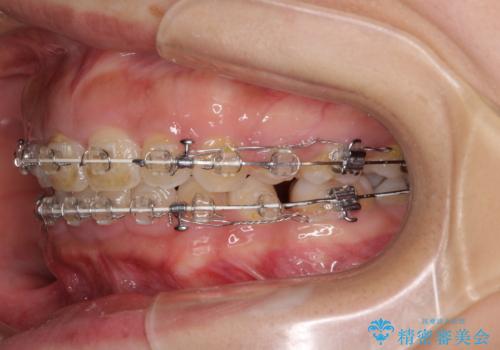

- 矯正装置

- 審美装置

- 口元の突出感と口の閉じにくさを気にして来院された患者様です。

上下左右の小臼歯4本を抜歯し、ワイヤー装置にて口元を引っ込めるよう矯正治療を行うこととしました。

上下顎ともに前突しており、特に上顎は著しい突出感でした。

また、下顎歯列には左右差があり、非対称な抜歯が必要と判断されたため、治療は困難なものとなりました。